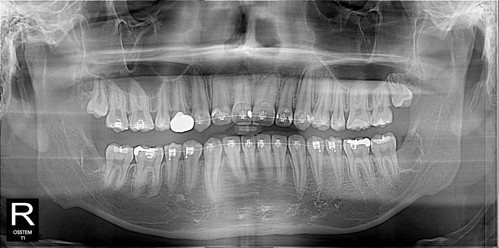

수면 마취가 효과가 잘 유지되었고 시간상 괜찮아 우측도 그 날 발치를 완료^^